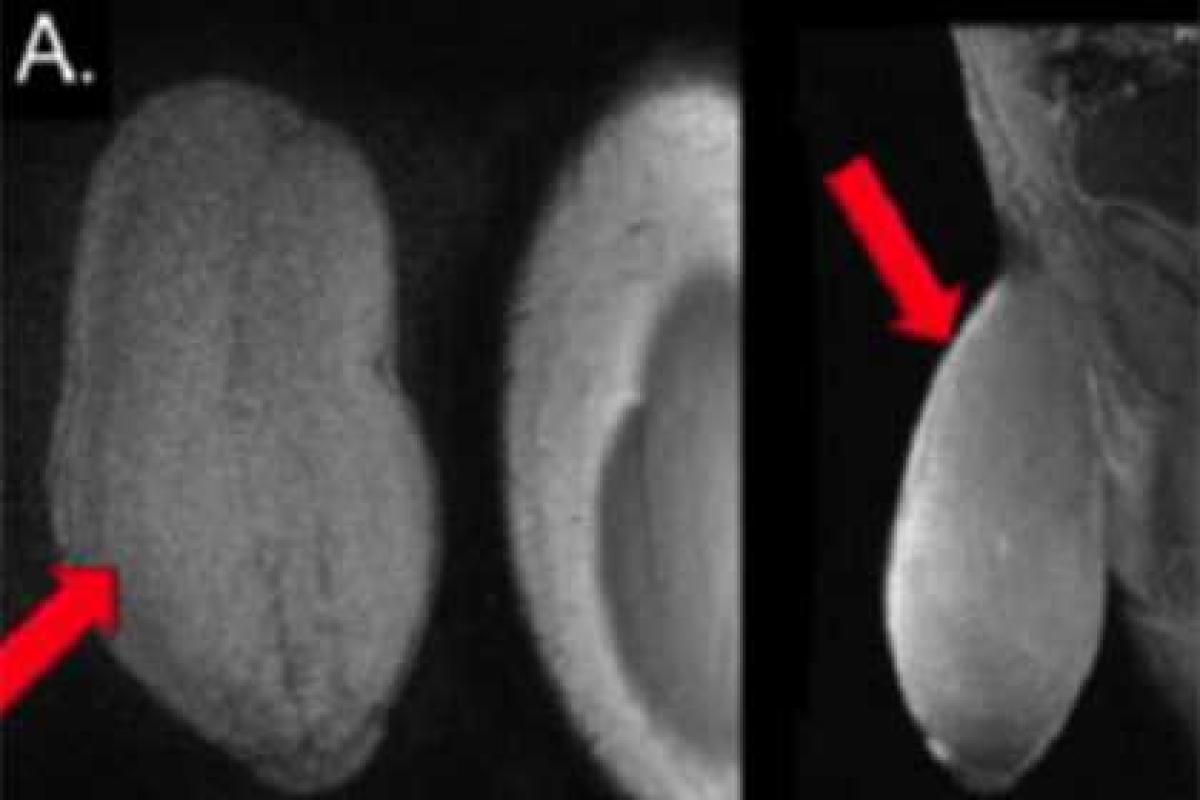

Отмечается, что хирурги были шокированы, когда молодой человек впервые пришел к ним на прием. После измерений выяснилось, что длина его пениса в неэрегированном виде составляет почти 18 сантиметров, а окружность — около 25 сантиметров. В возбужденном состоянии размер члена не увеличивался, однако юноша пожаловался, что не раз попадал в неловкие ситуации из-за нежелательной эрекции.

Доктор Рафаэль Кэррион (Rafael Carrion), который занимался лечением юноши, после изучения литературы и консультаций с коллегами принял решение сделать подростку операцию по уменьшению члена. The Daily Mail утверждает, что это первая подобная операция в мире.

После процедуры врачи не стали проводить замеры пениса пациента, однако констатировали, что «изменения были внушительными». Лечащий врач юноши отметил, что никаких заболеваний у подростка обнаружено не было. Отмечается, что подросток после проведенной операции был «в восторге».